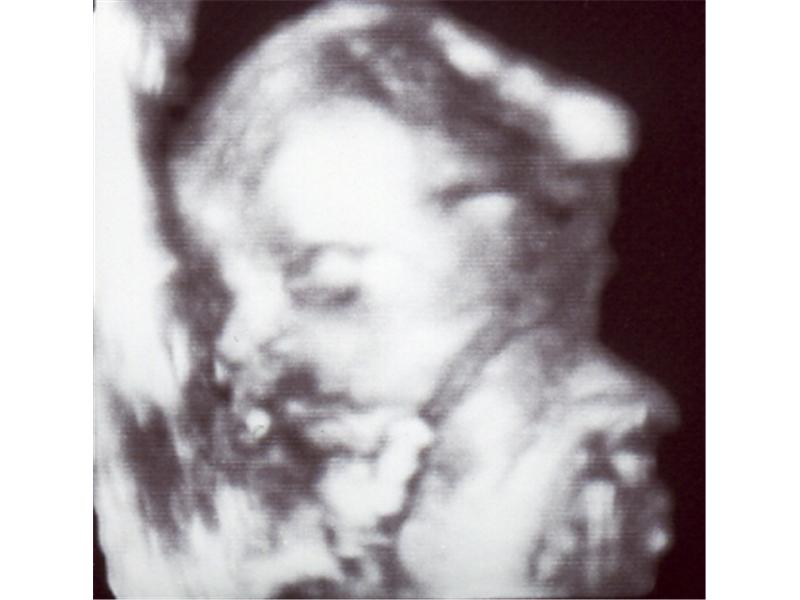

Snímky z ultrazvuku Volešákova miminka